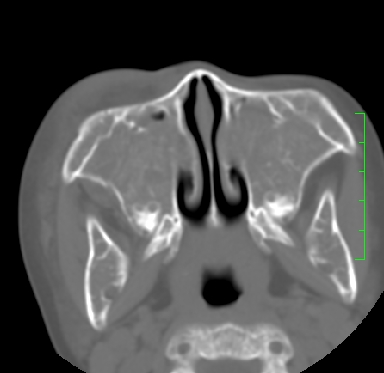

标题: PED1889:上颌窦病变

m,10y,外伤做ct